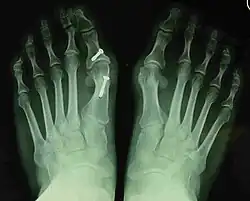

![]() Fig. 8a. Painful hallux valgus and metatarsus primus varus deformity recurrence of left foot after osteotomy surgery | |

- For recurrence correction after osteotomy procedure (Fig. 8)

Late deformity recurrence can happen after osteotomy (bone-breaking) procedures because osteotomy surgeries do not specifically stabilize first metatarsal bone.